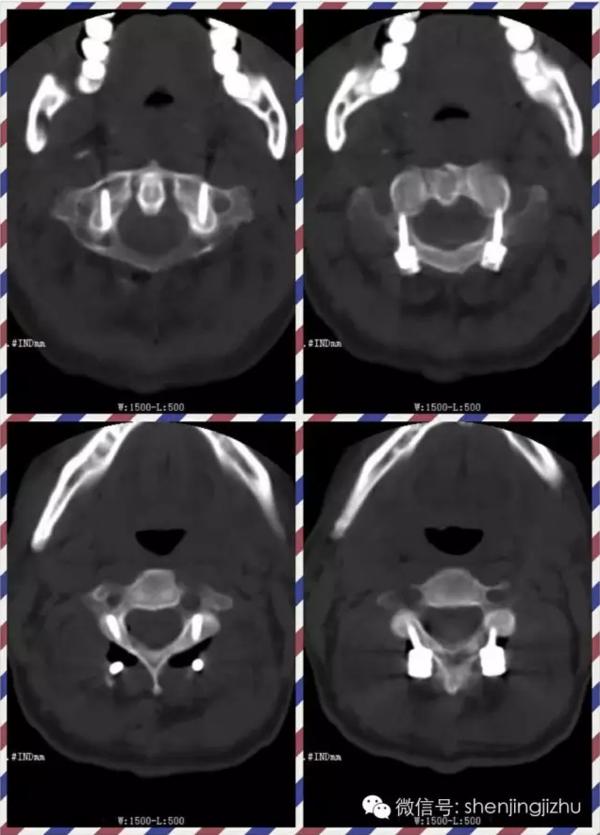

枢椎齿状突骨折枢椎前滑脱

图片尺寸600x338